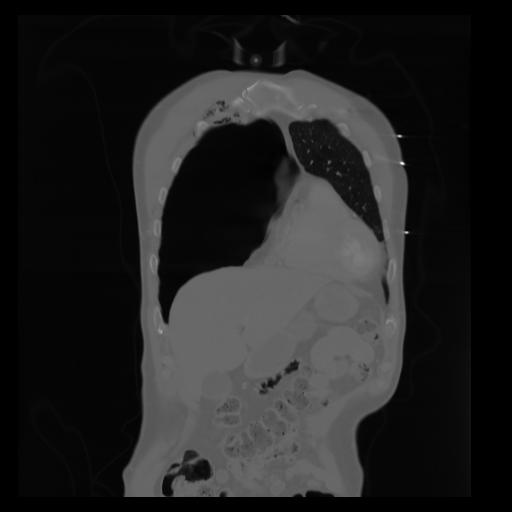

29 CUERPO,CE,Coronal,3.000,CUERPO,Coronal,